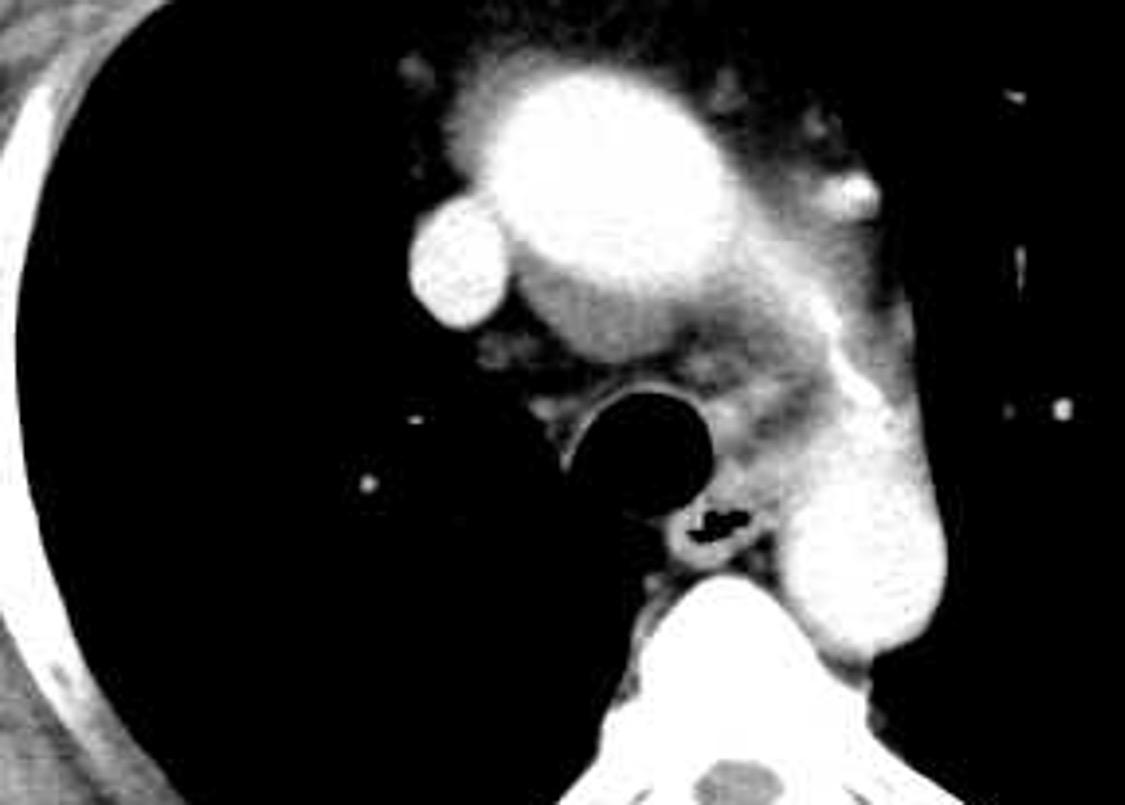

Aneurisma aórtico de localización poco habitual

Edad: 40-50 años

3% segregan catecolaminas.

(En el área Paravertebral +/-50%.)

Intenso realce con el contraste.

32 años .Preeclampsia a los 19. Hipertensión no controlada. Masa paravertebral sólida que se realza intensamente con afectación ósea.

Yue Y t al. Asymptomatic left posterior mediastinal functional Paraganglioma. A case report. Medicine . 2019